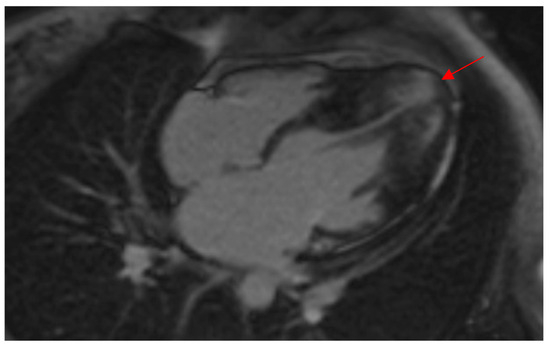

Morphologically, ApHCM can be classified into two groups: “pure” ApHCM, characterized by isolated asymmetric apical hypertrophy, and “mixed” ApHCM (distal-dominant form), where there is coexistent hypertrophy of the interventricular septum. Patients with the “mixed” ApHCM pattern have to demonstrate the greatest wall thickness in the apical segments (Figure 2). Recent studies [14,15] have shown that the occurrence of HCM-related adverse events was significantly higher in the distal-dominant group compared to the pure apical group.

Figure 2. CMR demonstrates a thickened LV apex in a female patient of this study with wall thickness extending to the midventricular septum, indicating a “mixed ApHCM” (distal-dominant form). Note the presence of LGE in the hypertrophied apex (red arrow) as well as the apical aneurysm. ApHCM, apical hypertrophic cardiomyopathy; CMR, cardiac magnetic resonance imaging; LGE, late gadolinium enhancement; LV, left ventricular.